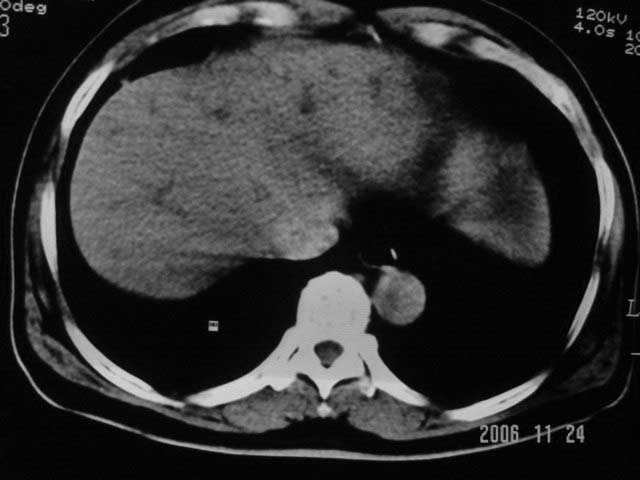

标题: CT5395:男、60岁,皮肤、巩膜黄染伴上腹部疼痛20天 [打印本页]

标题: CT5395:男、60岁,皮肤、巩膜黄染伴上腹部疼痛20天

劳烦各位老师看一下最后一幅箭头指的地方是不是胆总管结石.ct值约63hu.

感觉不是结石可能,与上一层面联系应该是门脉区影像,图像显示不佳,胆总管显示不清[特别是胰头以上段],目前影像只能说肝内外胆管扩张,胰管扩张,胆囊扩大。提示胆总管远端梗阻。可考虑肿瘤或结石所致

胆总管内结节状高密度灶,边缘隐约可见低密度环绕,首先考虑结石伴肝内胆管扩张; 2、胆囊增大,胆囊炎

肝内外胆管及胰管均示有扩张,胆囊增大.提示胆总管远端梗阻,可考虑肿瘤或结石或肿瘤伴结石,建议强化扫描